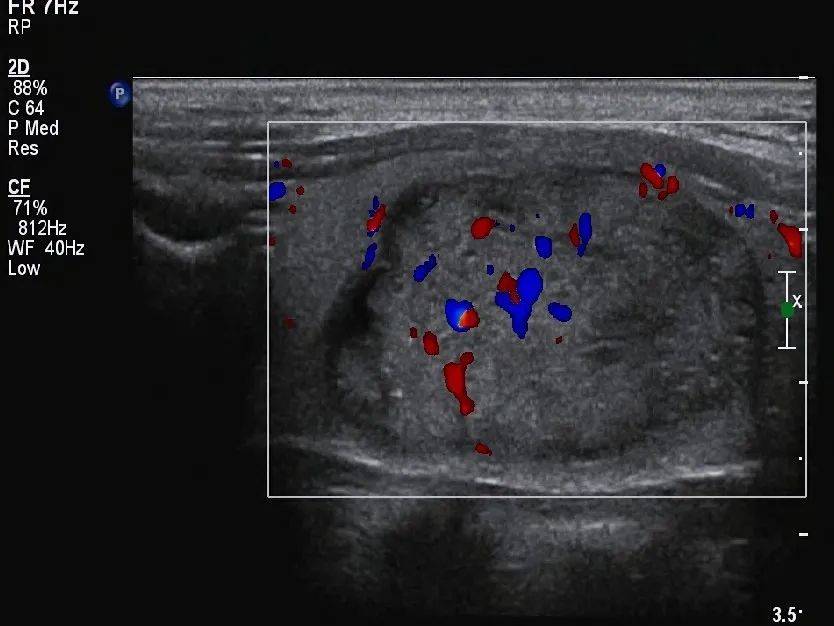

甲状腺形态失常,左侧叶增大,内部回声不均匀,见囊实混合性结节,大小约 33mm×19mm×28mm ,形态规则,边界清,纵横比 <1 ,内部以实性为主,实性部分见少许散在点状强回声(图 1 、图 2 ),结节周边伴低回声声晕,声晕厚度不均匀(图 3 ), CDFI:结节周边见环绕血流信号,内部见不规则分布的血流信号,局部较丰富(图 4 、图 5 )。SMI:结节局部微细血流信号丰富(图 6 )。

图 4 CDFI 示内部可见血流信号